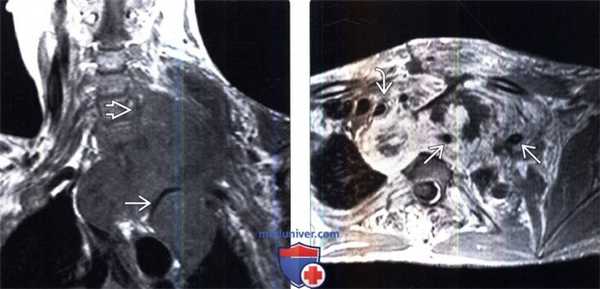

(Слева) На фронтальном Т1-ВИ пациента с НФ1 визуализируется крупная ЗООПН верхнего средостения и нижней части шеи, окружающая собой левую подключичную артерию и инфильтрирующая левое плечевое сплетение.

(Справа) На аксиальном Т1-ВИ с КУ у этого же пациента визуализируется крупная накапливающая контраст ЗООПН верхнего средостения, смещающая трахею вправо, окружающая левую подключичную артерию и распространяющаяся в левую надключичную ямку. Центральная неправильной формы зона, не накапливающая контраст, является участком некроза опухоли.